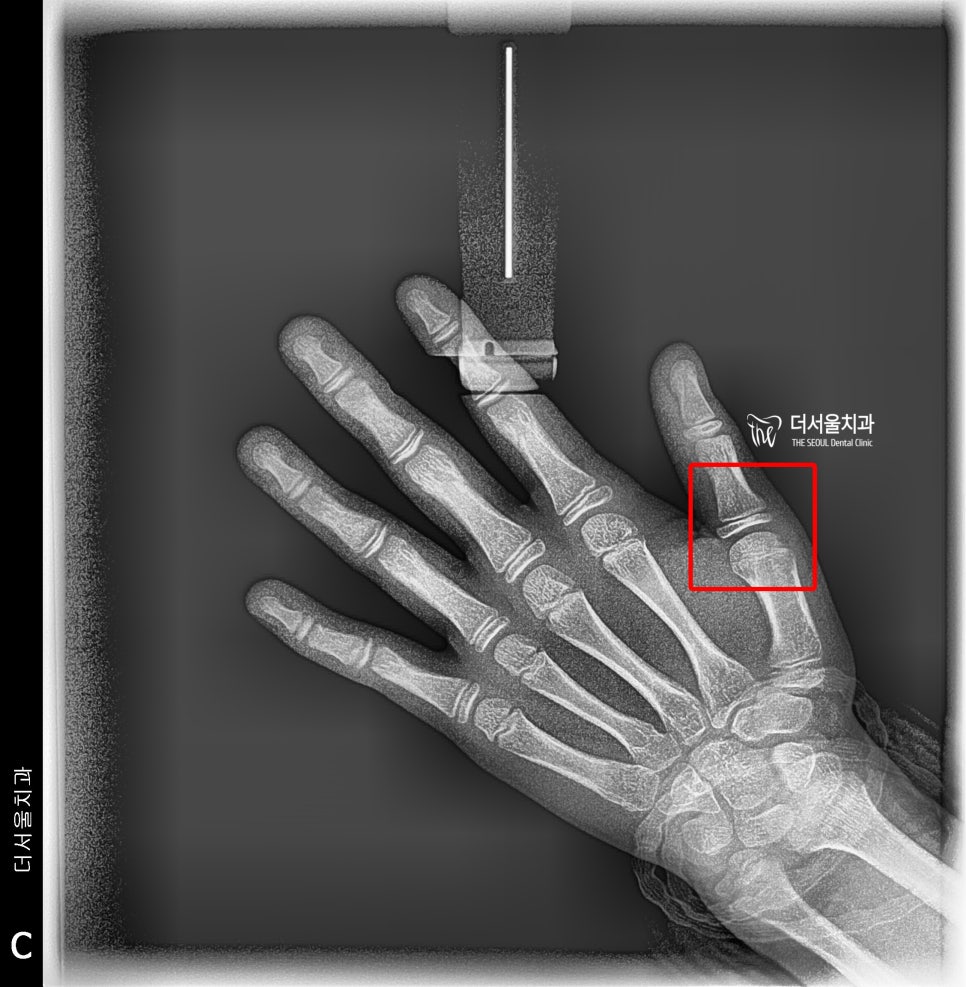

그래서 치료 계획 수립에 앞서,

먼저 성장판 검사를 하게 됩니다.

수완부 촬영인데,

아직 턱이 더 클 수 있다는 것을 뜻합니다.

(종자골이 없음)

성장도 이제 멈추셨습니다.

종자골이 만들어졌기 때문에

아마 턱도 이제는 성장이